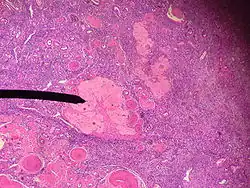

Corps albicans

Le corps albicans (ou corpus albicans) est aussi appelé corps blanc ou corps fibreux (la dégénérescence est fibreuse, les cellules glandulaires se transforment en tissu conjonctif dense[réf. nécessaire]). Il apparaît lors de la lutéolyse (en)) du corps jaune, à la fin de la phase lutéale ou, après que le placenta a pris le relais pour la production d'hormones.[réf. nécessaire]